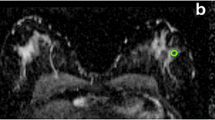

Dynamic contrast-enhanced breast MRI was performed on a 3.0-T clinical MR system (3.0T Achieva, Philips Healthcare, Best, The Netherlands). Patients were placed in prone position on a dedicated four-element SENSE-compatible phased-array bilateral breast coil (MRI devices, Würzburg, Germany) utilized for simultaneous imaging of both breasts. The MR protocol included an axial high-resolution T1-weighted fast gradient echo (HR-T1FFE) fat-suppressed series (TE/TR 1.7/4.5 ms; inversion delay SPAIR 130 ms; flip angle 10°; FOV 340 × 340 mm2, acquired voxel size 0.66 × 0.66 × 1.6 mm3, reconstructed voxel size 0.66 × 0.66 × 0.80 mm3), followed by an axial T2-weighted fat-suppressed series (TE/TR 120/9,022 ms; inversion delay SPAIR 125 ms; flip angle 90°; FOV 340 × 340 mm2, acquired voxel size 1.01 × 1.31 × 2.0 mm3, reconstructed voxel size 0.66 × 0.66 × 2.00 mm3). Finally, dynamic contrast-enhanced fat-suppressed T1-weighted images were acquired (TE/TR 1.3/3.4 ms; flip angle 10°; FOV 320 mm × 320 mm, acquired voxel size 0.91 mm × 0.91 mm × 2.00 mm, reconstructed voxel size 0.83 mm × 0.83 mm × 1.00 mm, temporal resolution 50 s per dynamic acquisition) with a total of six dynamic acquisitions, one obtained before, and five obtained 0, 60, 120, 180, and 240 s after administration of a bolus injection of 0.1 mmol/kg gadolinium-based contrast agent (Magnevist, Schering, Berlin, Germany) followed by a 20-ml saline flush at an injection rate of 3 ml/s with an automatic injector.

MR images were interpreted by two breast radiologists with more than 10 years of experience and were used to derive the location of the lesions. A region of interest (ROI) was drawn at the lesion site location for all four optical absorption images (e.g., see Fig. 2). For comparison, a similar ROI was drawn at the mirror image lesion site location of the contralateral breast, where no lesion was found. The visibility of the lesions on DOT was assessed both quantitatively and qualitatively. Quantitative values were computed from the volume images of the optical absorption coefficient obtained from the DOT system. The mean absorption coefficient of the ROI was divided by the mean absorption of the background, which included the rest of the breast on that slice except for the lesion (the quantitative score). Qualitative scores for contrast relative to background were given independently by two readers for every ROI, on a scale from −4 to 4, where: 0 = no visibility; 1 = slight heterogeneity seen at the site of the known lesion; 2 = moderate contrast, but less/more than other structures, seen at the site of the known lesion; 3 = contrast at the known lesion site comparable to that of other structures; 4 = major contrast at the known lesion site; a minus sign was used if the signal at the ROI was lower than the background, and a plus sign when it was higher. To learn how to score the images, readers were shown an example set of classified images (not from the study population) before they started the scoring process. All images were made anonymously, placed in random order, and scored by two readers separately, without knowledge from other examinations. Images were scored again after 3 months in a second independent reading by the two investigators.

Examples of ROIs on DOT images compared with MRI. a Patient is a 60-year-old woman with lesion in the right breast; BI-RADS category 2 on MRI (left image T2-weighted MRI with fat suppression); visibility score −4 on DOT (right image); final diagnosis, benign cyst. b Patient is a 56-year-old woman with lesion in the right breast; BI-RADS category 5 on MRI (left image DCE-MRI); visibility score +4 on DOT (right image); final diagnosis, invasive ductal carcinoma